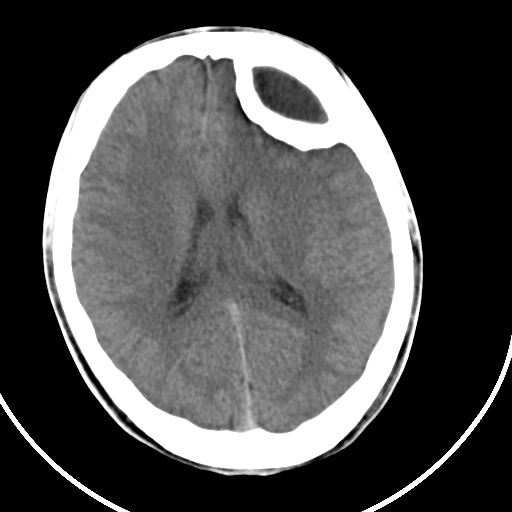

标题: CT21939:男20岁,外伤一年后,现头疼. [打印本页]

标题: CT21939:男20岁,外伤一年后,现头疼.

硬膜外血肿机化

硬膜外血肿伴包膜钙化

左侧额部硬膜外血肿机化、骨化。

左侧额部硬膜外血肿机化、骨化